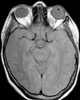

Acinic cell tumor

Acinic cell carcinoma is a malignant tumor representing 2% of all salivary tumors. 90% of the time found in the parotid gland, 10% intraorally on buccal mucosa or palate. [Source: Wikipedia ]